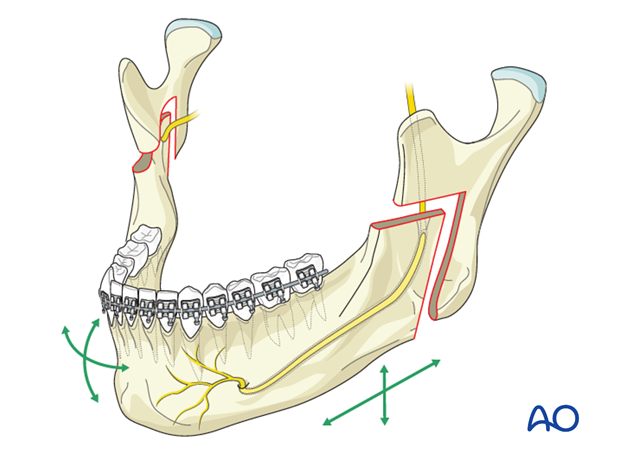

does reverse L osteotomy affect the ramus? i thought it cuts just near the ramus therefore it can give you longer mandible and different gonial but ramus stays the sameim thinking reverse L osteotomy for a longer ramus

does reverse L osteotomy affect the ramus? i thought it cuts just near the ramus therefore it can give you longer mandible and different gonial but ramus stays the same

View attachment 4456822

i’m not really sure, but like in this pic doesn’t it leave ramus the same?